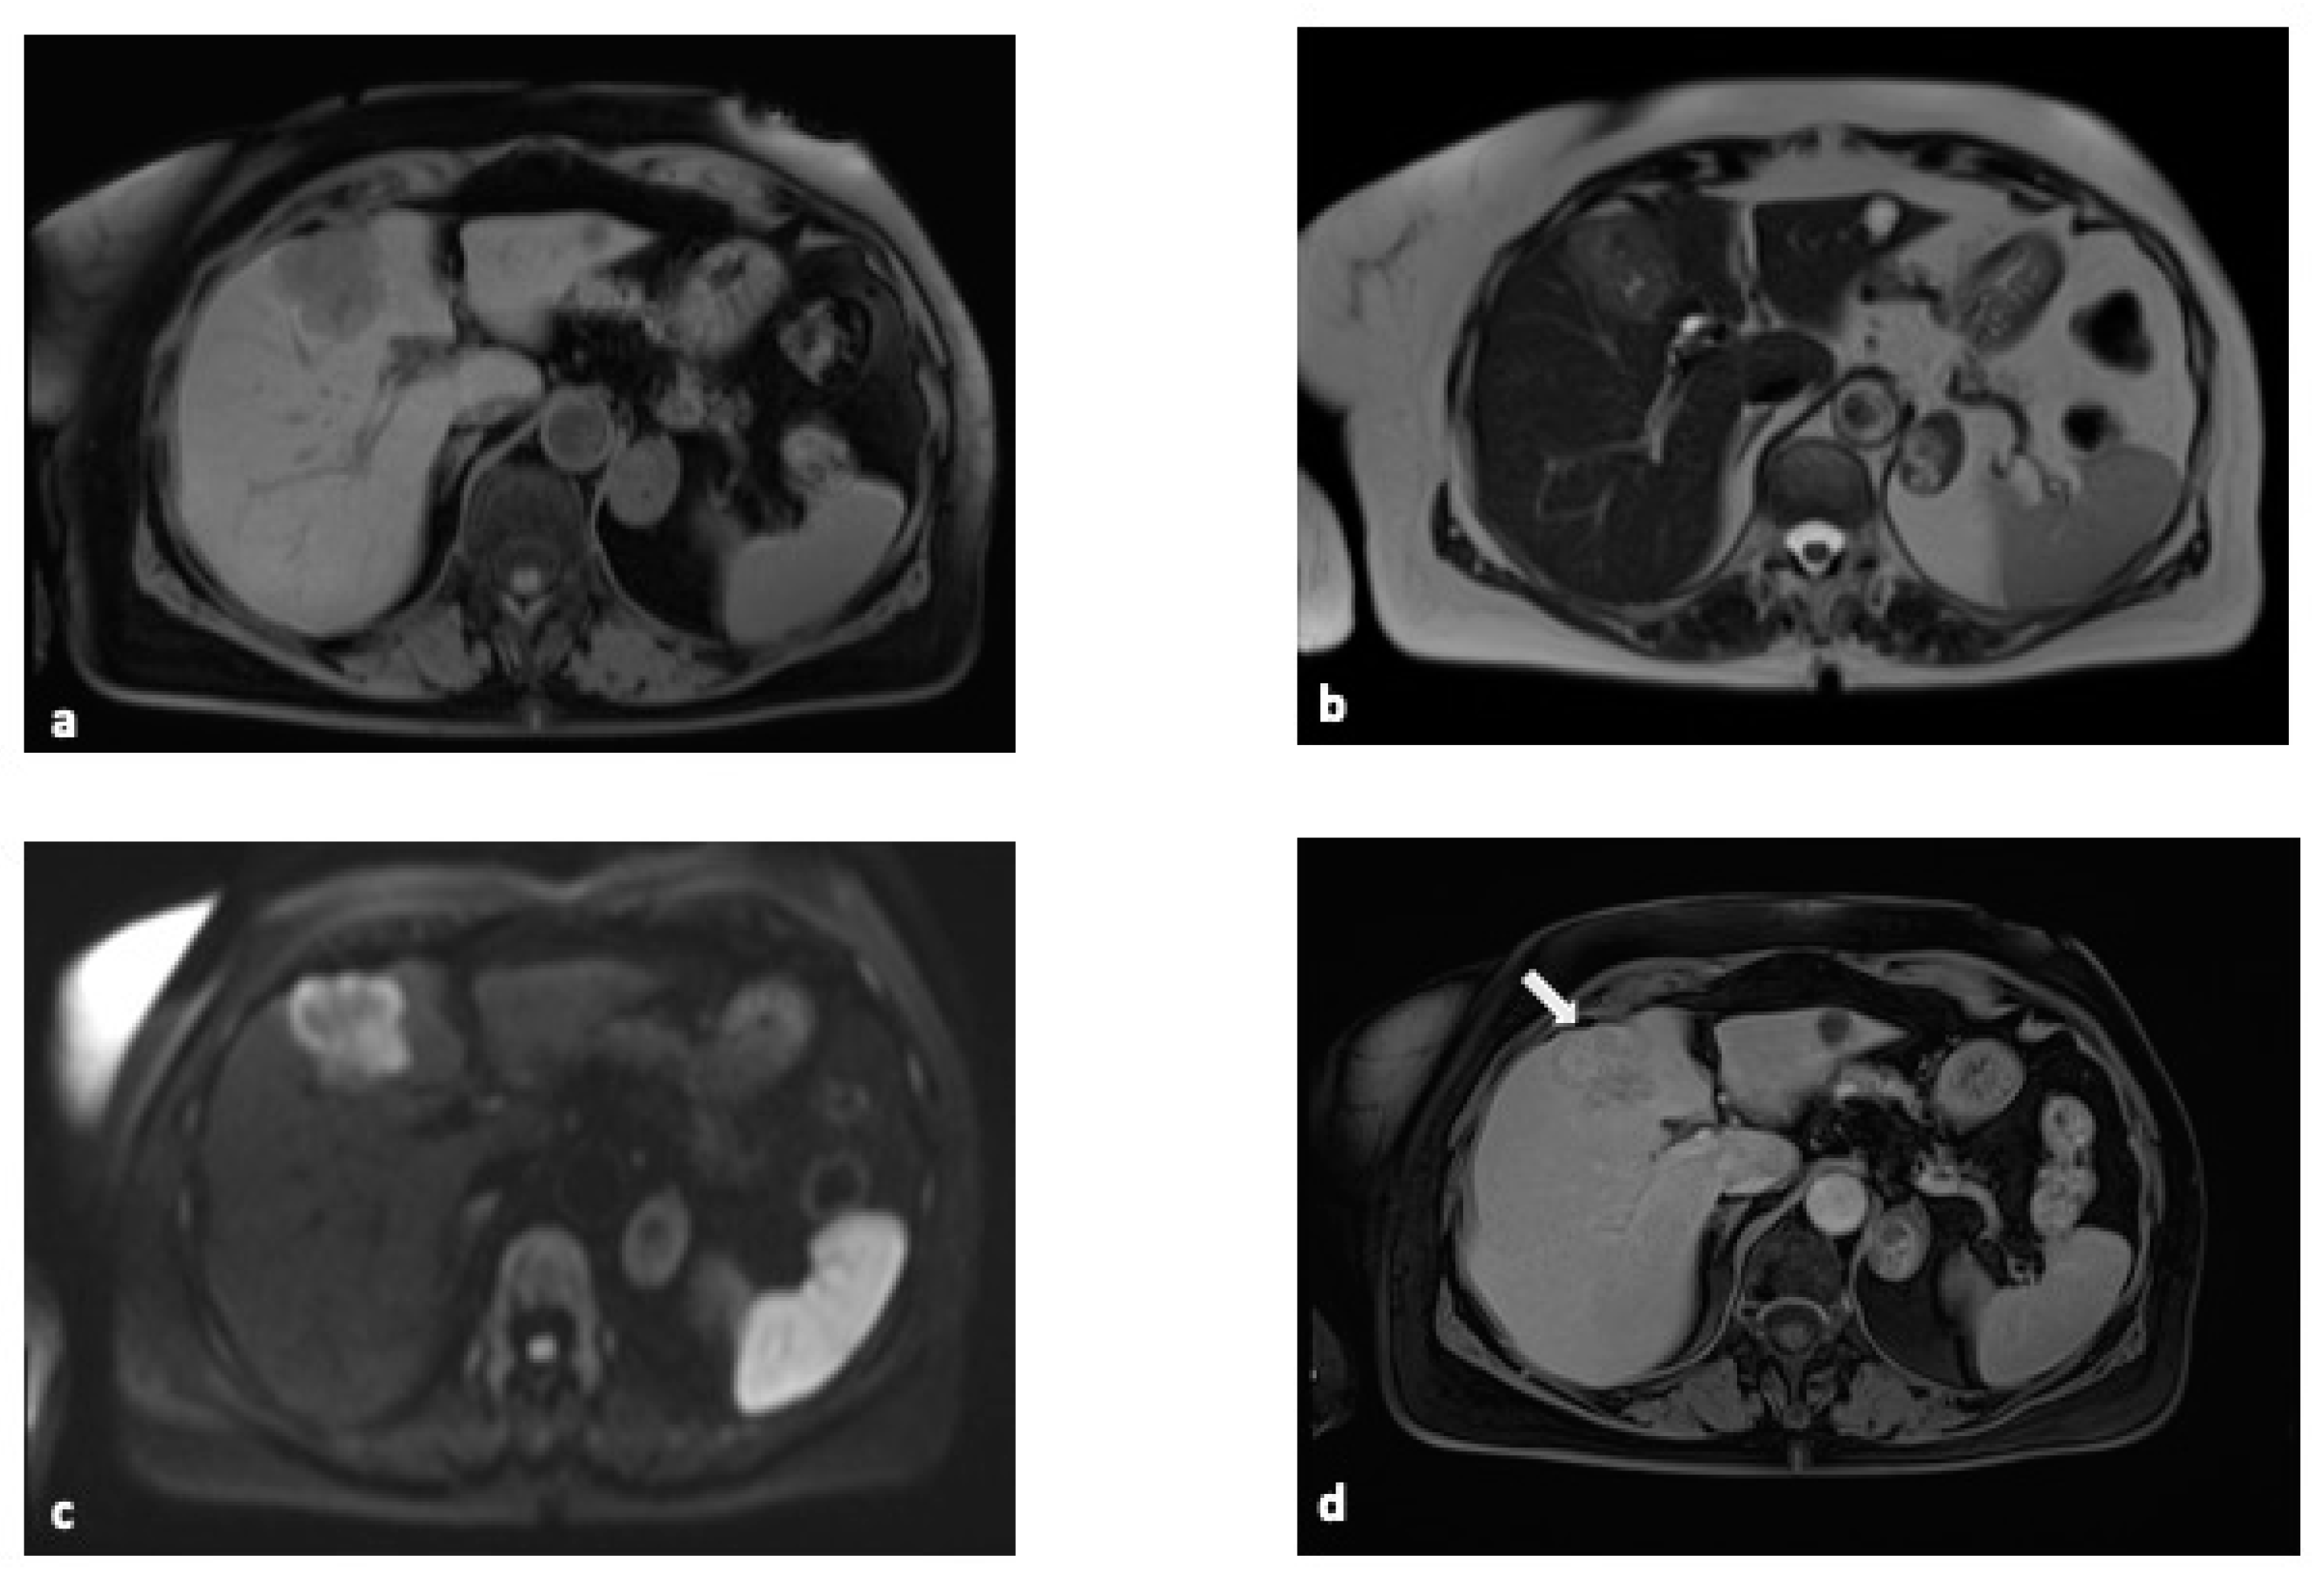

2.3. Magnetic Resonance Imaging (MRI)

| Magnetic Resonance (MR) | Excellent soft tissue contrast, superior for biliary tract evaluation. | High cost, longer exam time, and limited availability. | 85–95% | 80–90% | 85–90% | 85–95% |

- Jhaveri, K.S.; Hosseini-Nik, H. MRI of cholangiocarcinoma. J. Magn. Reson. Imaging 2015, 42, 1165–1179. [Google Scholar] [CrossRef] [PubMed]

- Kang, Y.; Lee, J.M.; Kim, S.H.; Han, J.K.; Choi, B.I. Intrahepatic mass-forming cholangiocarcinoma: Enhancement patterns on gadoxetic acid-enhanced MR images. Radiology 2012, 264, 751–760. [Google Scholar] [CrossRef] [PubMed]